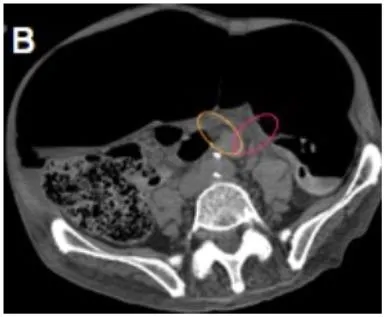

Whirl pattern, caused by the dilated sigmoid colon around its mesocolon & vessels

Bird-beak appearance of the afferent and efferent colonic segments

Whirl sign

Bird beak sign

X-marks-the-spot sign : complete obstruction 되면서 distal, proximal sigmoid colon이 둘 다 obstruction 되는데, 이 두 속의 transition point가 반대로 나타나서 마치 x표시 같다.

Split wall sign : incomplete obstruction, partial obstruction시 distal, proximal colon 사이 mesenteric fat이 들어가며 마치 둘을 분리시키는 것 같다